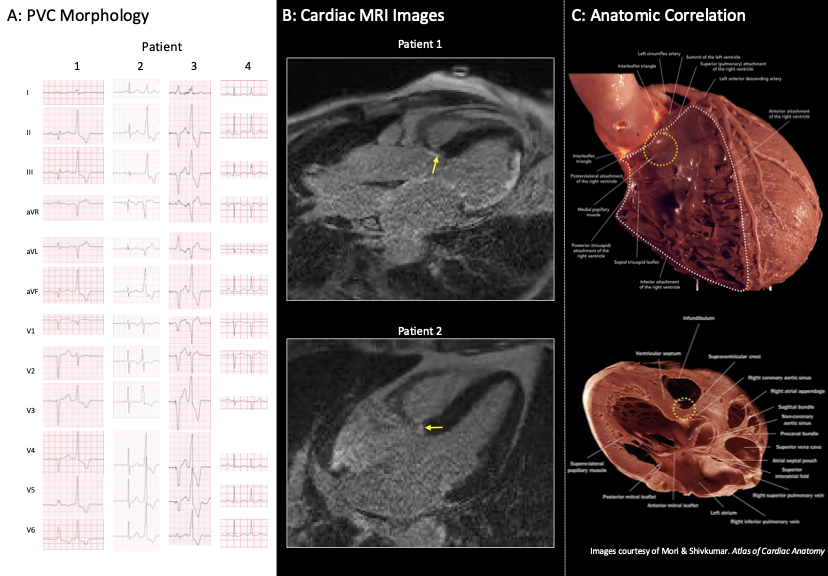

Results: A total of 4 patients were identified with elevated PVC burden prior to the development of CHB,

without reported septal scar on CMR. Each had a single PVC morphology which was left bundle branch

morphology, V3/V4 transition, with left inferior axis with R or Rs morphology in lead 1 (Figure 1A), and all

developed infrahisian CHB. PVC characteristics most closely matched PVCs originating from the right

coronary cusp (RCC) and basal septum. Careful review of the CMR images in 2/4 (50%) patients found an

area of focal fibrosis at the basal septum at the junction RCC and medial papillary muscle of the right

ventricle (Figure 1B).In the other 2 patients, this area was not well imaged.

Conclusion: We identified a consistent PVC morphology in patients who developed infrahisian CHB with

imaging correlate of focal fibrosis at the site where the His bundle and proximal left and right bundles

traverse (Figure 1C). This focal area of scar is in a site that is difficult to image by CMR, and often only

visualized in one view and hence easily missed. This study demonstrates the need for careful electro-

anatomic-imaging correlation in patients with frequent PVCs of this morphology.